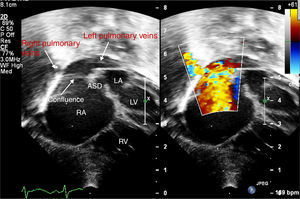

Echocardiography confirmed situs solitus and levocardia. All four pulmonary veins were imaged forming a confluence which opened directly into the right atrium with a mean gradient of 8 mmHg (Figures 1–3). There was no vertical vein and the coronary sinus was normal. Individual pulmonary veins were adequately sized. The ASD was of ostium secundum type, measuring 4.7 mm, with mildly restrictive peak and mean gradients of 5 and 1 mmHg, respectively. Surgical exploration revealed all pulmonary veins draining to the right atrium with a shelf over the opening of the left pulmonary veins. The patient underwent primary sutureless TAPVC repair and closure of the ASD with a tanned pericardial patch, and is doing well.